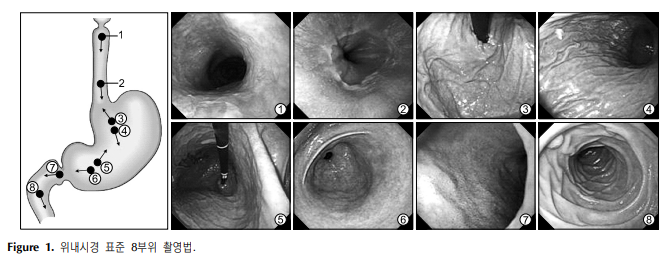

내시경 검사시 표준 촬영 부위 본문

위내시경 :

① 상부식도, ② 위식도접합부,

③ 분문부, ④ 위 소만측의 상부, ⑤위각부, ⑥전정부,

⑦ 십이지장 구부, ⑧ 십이지장 제2부